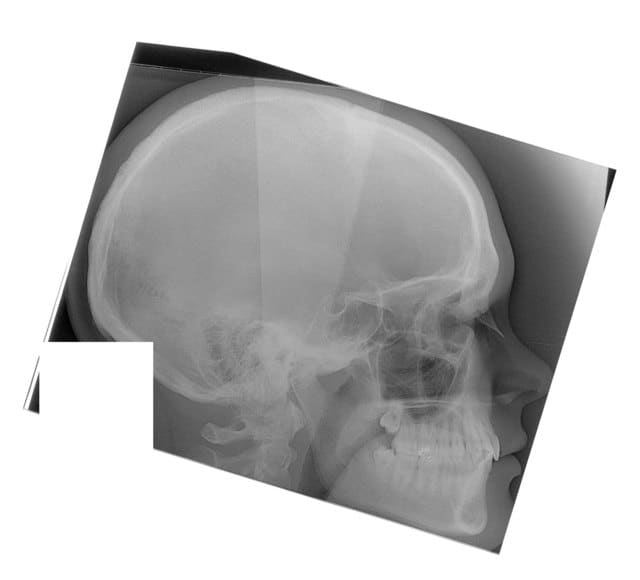

Tele2002 qhiepn - Eugenol

Tele2007 b6yul0 - Eugenol